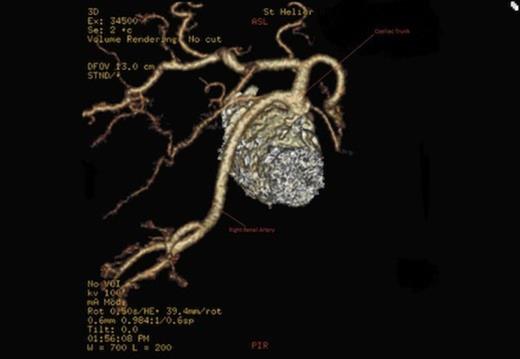

A CT scan revealed an aneurysmal distal thoracic aorta measuring 40mm and 49mm at the level of the diaphragm and of normal calibre at the left renal artery. The right renal artery very interestingly had its origin from the coeliac axis with no significant renal artery disease and the left renal artery showed calcific disease with post-stenotic dilatation at its ostium from the aorta. There were also no accessory renal vessels noted.